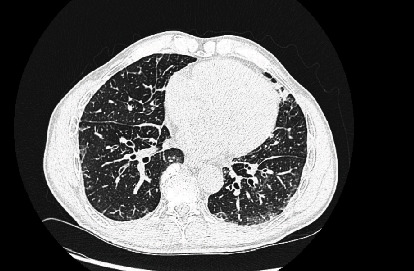

Background: Lymphangitic carcinomatosis (LC), a hallmark of advanced metastatic cancer with a poor prognosis, primarily impacts the lymphatic system of the lungs, manifesting as progressive breathlessness, cough, or hemoptysis. While prostate cancer commonly metastasizes to bones and regional lymph nodes, lung involvement is rare. This case features a patient in generally good health who presented with an insidious dry cough, leading to a diagnosis of Stage 4 prostatic adenocarcinoma with rare lymphangitic spread to the lungs. Case Presentation: A 70-year-old male in good health presented with chest tightness, a dry cough, and sudden left testicular swelling. Imaging revealed interstitial lung markings, severe left hydronephrosis, and prostatomegaly. A prostate biopsy confirmed adenocarcinoma. A PET-CT scan raised significant concern for LC, prompting the initiation of urgent inpatient chemotherapy with docetaxel. Conclusion: LC is a metastatic pattern commonly associated with solid tumors, particularly breast, gastric, and lung cancers. Its occurrence in prostate cancer is exceptionally rare. This condition is typically linked with advanced disease and a poor prognosis, often serving as a critical indicator of an underlying malignancy that may otherwise go undetected.

背景:淋巴管癌肿(LC)是预后不良的晚期转移性癌症的标志,主要影响肺部淋巴系统,表现为进行性呼吸困难、咳嗽或咯血。虽然前列腺癌通常会转移到骨骼和区域淋巴结,但肺部受累的情况并不多见。本病例中的患者总体健康状况良好,但出现隐匿性干咳,最终被诊断为前列腺腺癌 4 期,并伴有罕见的肺部淋巴管转移。病例介绍:一名 70 岁男性,健康状况良好,因胸闷、干咳和突发性左侧睾丸肿胀就诊。影像学检查发现肺间质性病变、严重的左肾积水和前列腺肿大。前列腺活检证实为腺癌。PET-CT 扫描显示该患者患有 LC,这促使他接受了多西他赛住院化疗。结论LC 是实体瘤(尤其是乳腺癌、胃癌和肺癌)常见的转移模式。在前列腺癌中出现这种情况极为罕见。这种情况通常与晚期疾病和不良预后有关,通常是潜在恶性肿瘤的一个重要指标,否则可能无法发现。